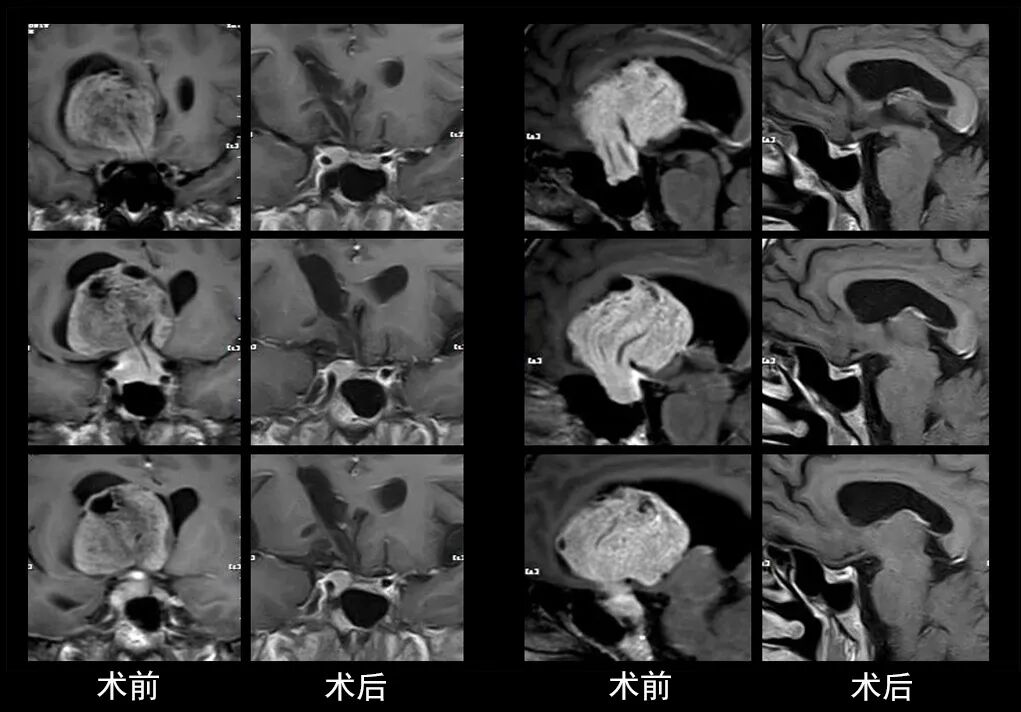

本研究中采用联合手术策略的代表性病例展示:

case 5

case 6